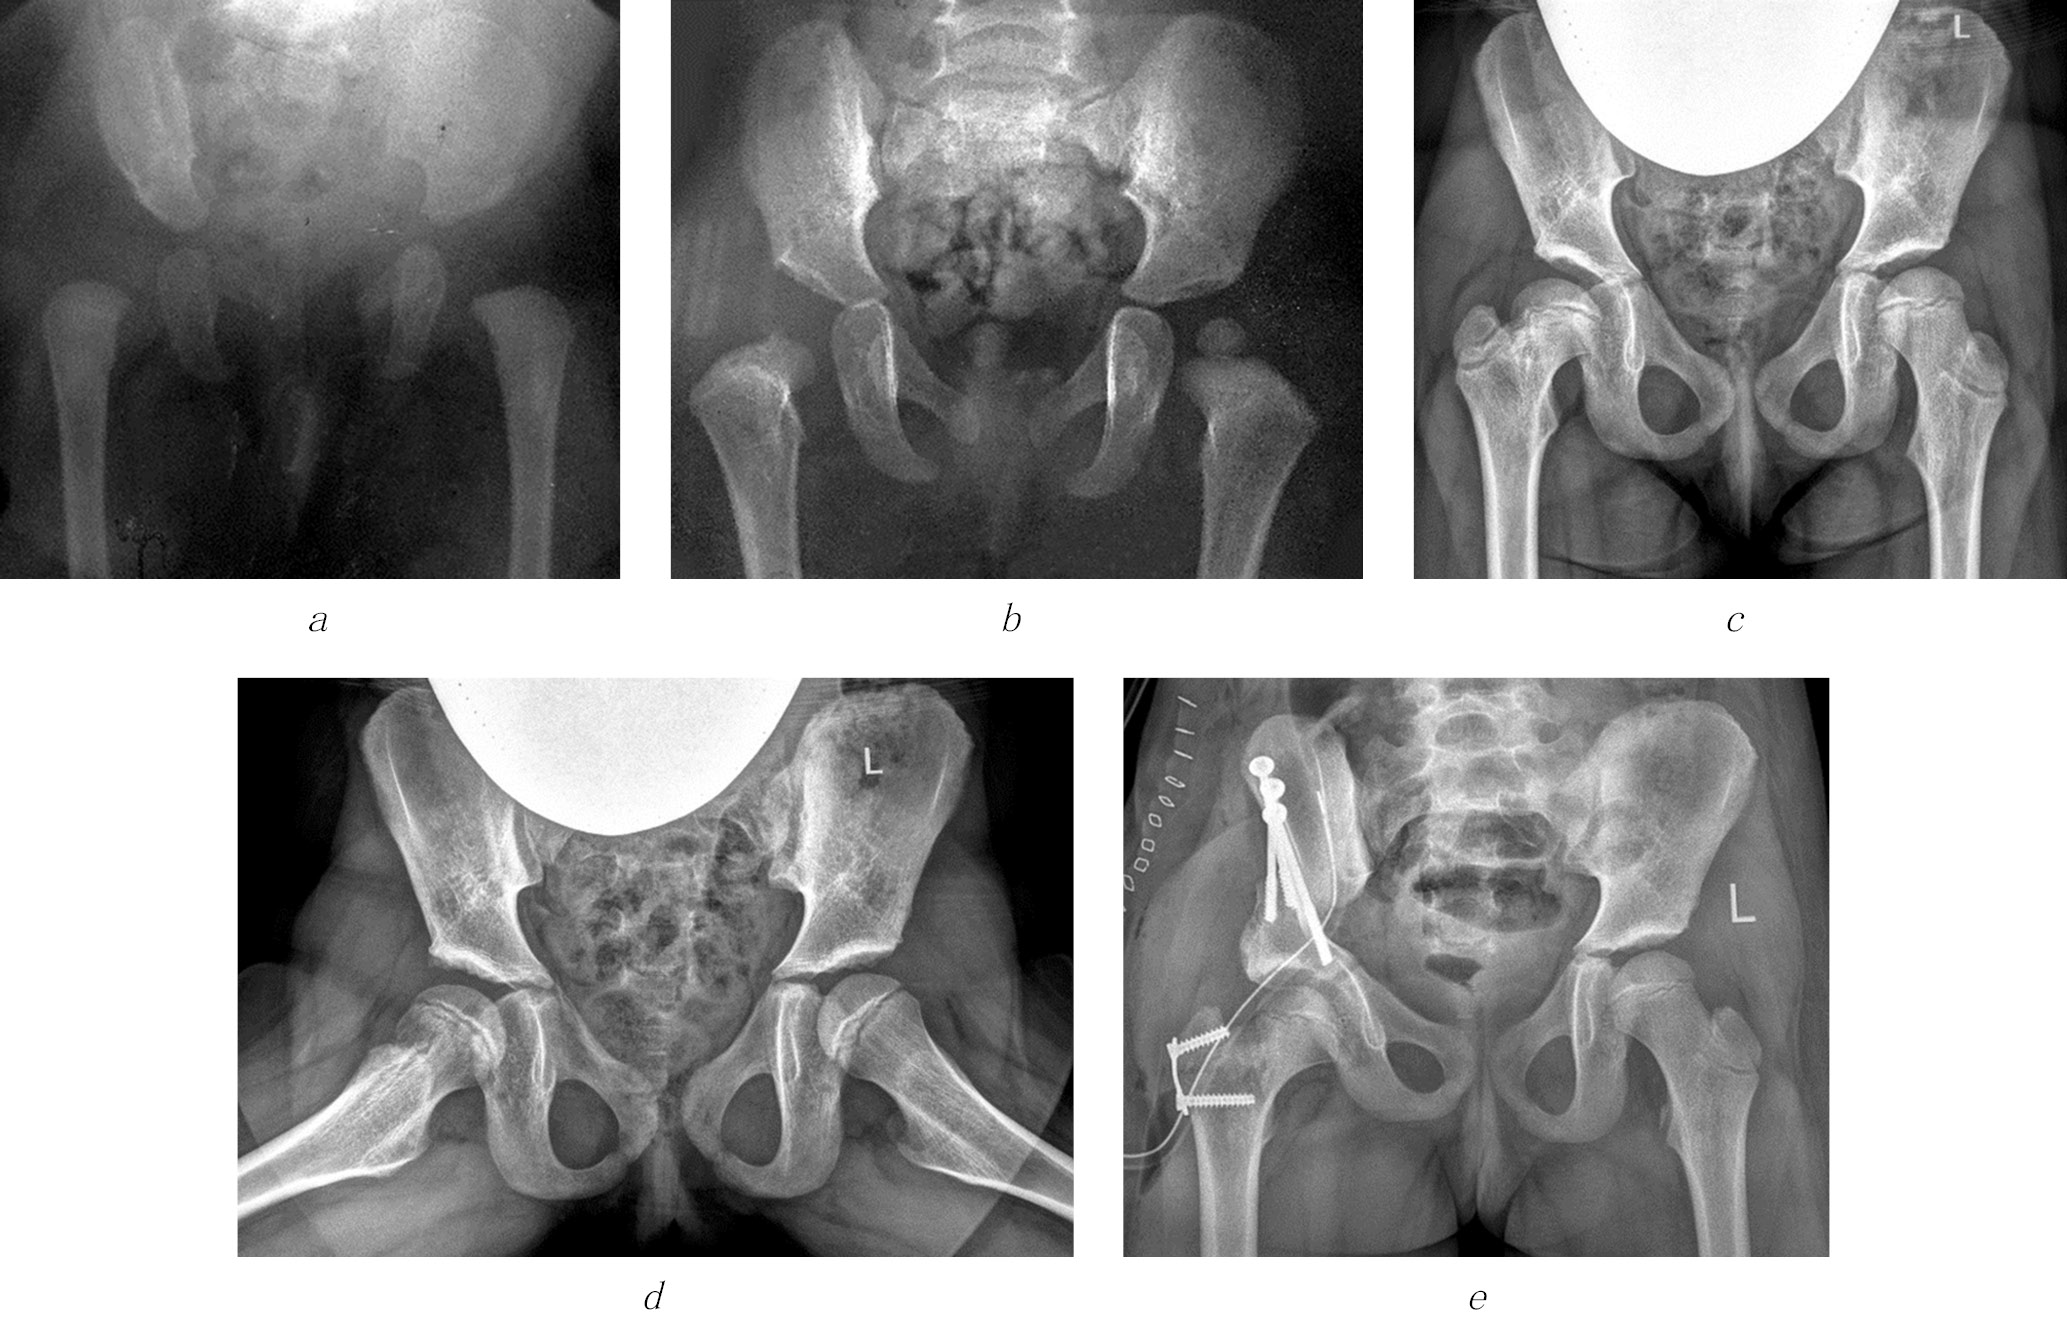

Fig. 2. Radiographs of patient G (4 years old) diagnosed with complications of septic arthritis of the hip joint, emerging high position of the greater trochanter on the right, and multiplanar deformity of the femoral neck with eccentric growth of the epiphysis posteriorly: a, b, before surgery; c, immediately after trochanteric epiphysiodesis on the right